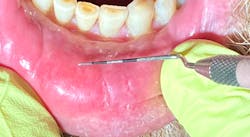

Clinically, the lesions were generalized, more prominent in the posterior buccal vestibular areas. White patches and collective striations were seen, measuring from 4 mm to 12 mm in size. They were painful to the touch and did not rub off with gauze. The patient said he noticed the start of the lesions on the tip of his tongue and on his lower lip, which appeared to be cracked and dry. See accompanying images.